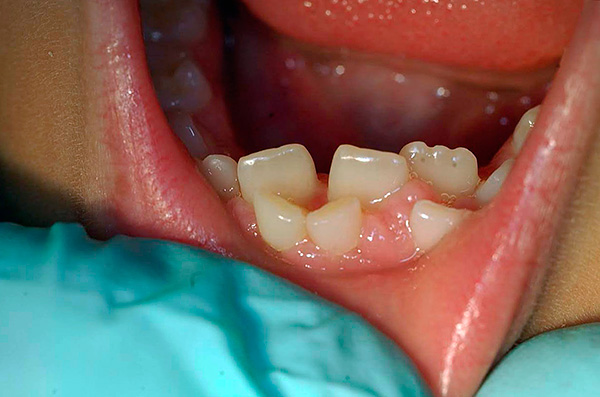

- Ciò che è importante sapere sulle caratteristiche dell'estrazione dei denti da latte nei bambini e quali fattori possono influire in modo molto significativo sul prezzo in questo caso;

Cosa devi sapere sulle caratteristiche dell'estrazione dei denti da latte

A differenza dei denti permanenti, i denti primari spesso non sono difficili da rimuovere, tuttavia, se parliamo solo del lato tecnico del problema. Se consideriamo il processo nel suo insieme, alcune circostanze lasciano un'impronta significativa nella politica dei prezzi nelle cliniche in cui esiste un servizio simile.

Ma prima di passare a considerare il costo della rimozione dei denti decidui, vediamo in quali casi potrebbe essere necessaria la loro rimozione:

- L'incapacità di ripristinare la parte della corona, completamente distrutta dalla carie;

- La formazione di una cisti sulla radice (s);

- Il rischio di diffusione dell'infezione da parodontite, quando esiste una minaccia al germe di un dente permanente;

- Complicanze della parodontite (periostite, ascesso, flemmone, ecc.);

- Ritardo del "riassorbimento" della radice, che crea ostacoli all'eruzione di un dente permanente;

- La comparsa di un dente permanente (lato) con la piena esistenza del latte;

- Cambio fisiologico dei denti.

E una serie di altre situazioni.